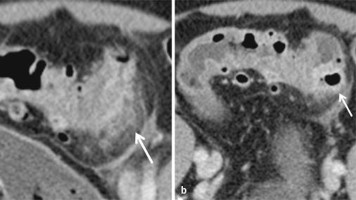

Welche Operation bei Sigmadivertikulitis im Alter?

Ob bei komplizierter Sigmadivertikulitis eine Hartmann-Operation oder eine Sigmaresektion mit primärer Anastomosierung und vorgeschaltetem Ileostoma vorgenommen wird, kann Medicare-Daten zufolge auch bei älteren Menschen individuell entschieden werden.